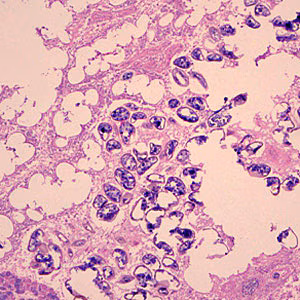

. In the definitive host, the plerocercoid develops into adult tapeworms in the small intestine. Adult diphyllobothriids attach to the intestinal mucosa by means of two bilateral groves (bothria) of their scolex

. The adults can reach more than 10 m in length, with more than 3,000 proglottids. Immature eggs are discharged from the proglottids (up to 1,000,000 eggs per day per worm) and are passed in the feces. Eggs appear in the feces 5 to 6 weeks after infection.

Mature diphyllobothriids are large tapeworms reaching 2—15 meters in length, with occasional larger specimens. The scolex always has two bothria (grooves). The general size and shape of the scolex may be subject to intraspecific variability, though some species-level differences have been described historically. Proglottids are broader than long, with a single genital pore that opens in the middle of the ventral surface; fully mature specimens may be comprised of a 2,000—5,000 proglottids. The ovaries are characteristically rosette-shaped.